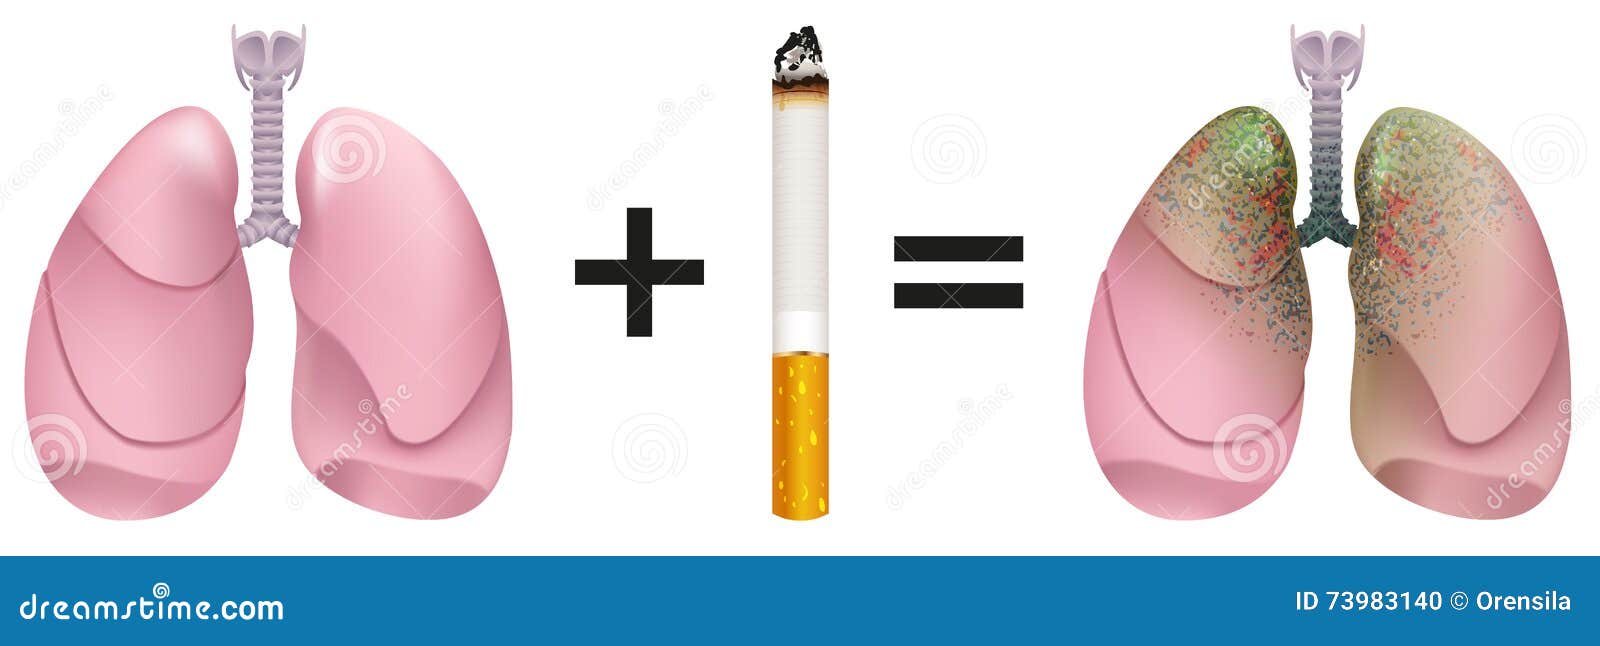

Здоровые Легкие Картинки

Здоровые Легкие Картинки 117 фото